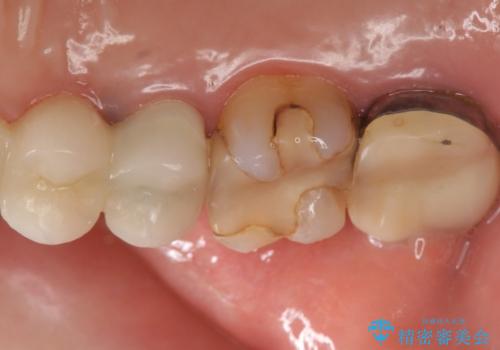

- 左上の奥歯がたまにしみるとのことで来院。視診・レントゲン画像より明らかに劣化した不適な修復物を確認しました。

同じ材料で同じように修復し直してもまた同じような予後になることが予想されるため、適合の良いセラミックインレーでの治療を提案させていただきました。

しかし向かい合わせになる歯の咬みこみが強く、インレーでは破折してしまうリスクが高いと予想し、より強固なクラウンで修復することになりました。